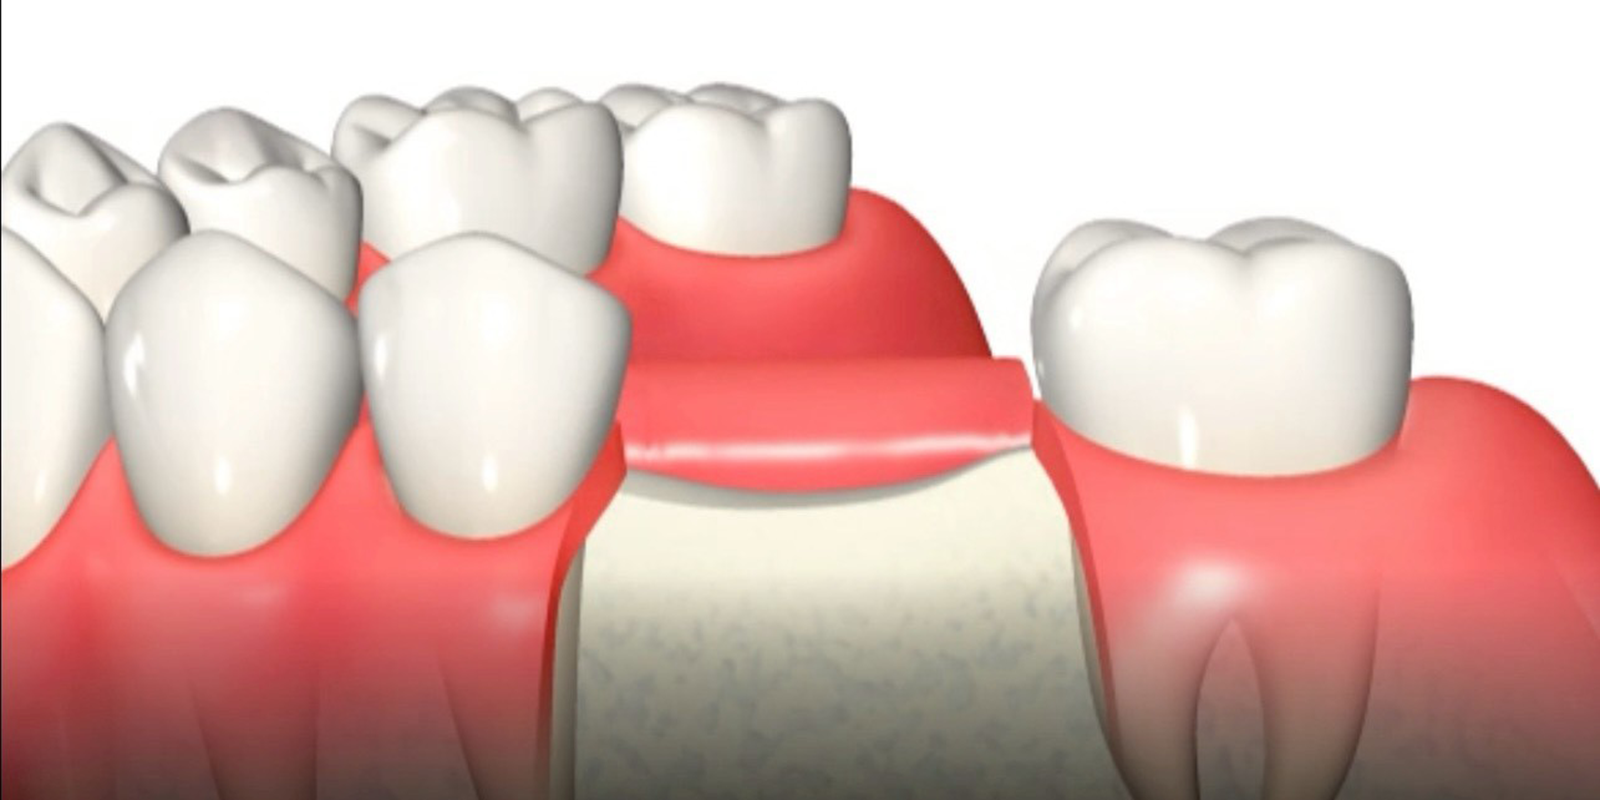

切開・剥離

切開が終わったら、頬側の粘膜骨膜弁をしっかりと剥離していきます。